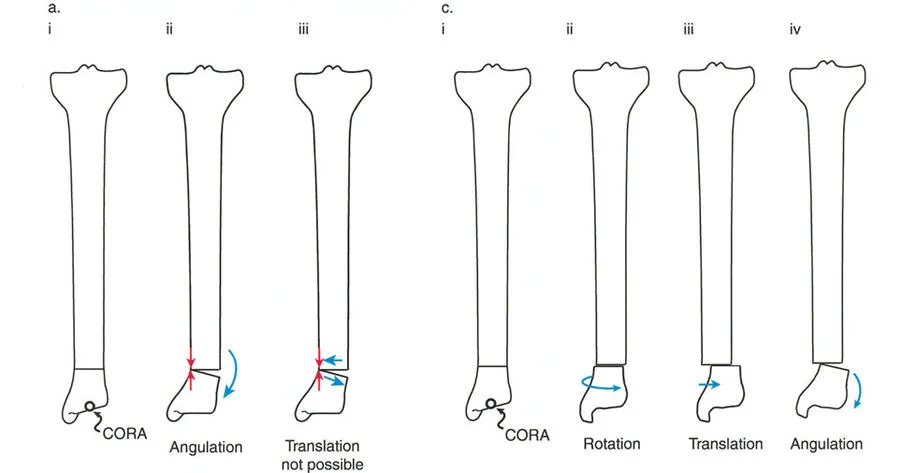

فهم قواعد بالي لقطع العظم أمر لا غنى عنه لتخطيط الإطار:

- قاعدة قطع العظم 1: عندما يمر قطع العظم ومحور تصحيح الانحراف (ACA) كلاهما عبر مركز دوران الانحراف (CORA)، فإن نهايات العظم ستنحرف دون ترجمة (انزياح). يتم استعادة المحور الميكانيكي، وتظل نهايات العظم متقاربة تمامًا، مما يخلق تصحيحًا كلاسيكيًا "إسفينيًا مفتوحًا" أو "إسفينيًا مغلقًا".

- قاعدة قطع العظم 2: عندما يمر محور تصحيح الانحراف (ACA) عبر مركز دوران الانحراف (CORA)، ولكن يتم إجراء قطع العظم على مستوى مختلف (غالبًا بسبب ضعف جودة العظم عند CORA أو مشاكل في الجلد)، فإن نهايات العظم ستنحرف وتخضع لترجمة محسوبة ومقصودة لإعادة محاذاة المحور الميكانيكي.

- قاعدة قطع العظم 3: (للاكمال) عندما يمر قطع العظم عبر مركز دوران الانحراف (CORA)، ولكن يتم وضع محور تصحيح الانحراف (ACA) خارج CORA، سيتم إنشاء تشوه ترجمة جديد، وهو خطأ شائع في وضع المفصلات غير المخطط له جيدًا.

في المنشآت القريبة من المفصل، غالبًا ما نعتمد على قاعدة قطع العظم 2. نظرًا لأنه لا يمكننا قطع العظم بأمان عند خط المفصل تمامًا (مركز دوران الانحراف CORA)، فإننا نقطع العظم في مستوى أدنى في منطقة الميتافيسيس. بعد تحقيق التصحيح الزاوي عبر المفصلات (محور تصحيح الانحراف ACA)، يتم إعادة محاذاة خطوط المحور الميكانيكي بشكل مثالي، ولكن نهايات العظم في موقع قطع العظم تتحرك بالنسبة لبعضها البعض.

قيود الأسلاك والدبابيس في القاعدة 2

لتحقيق هذه الترجمة الضرورية والمقصودة بسلاسة باستخدام إطار دائري كامل الأسلاك، يلزم استخدام أسلاك الزيتون المعاكسة (counter-opposed olive wires). تعمل أسلاك الزيتون كقوى سحب ديناميكية، تسحب قطعة العظم على طول الحلقة أثناء فتح المفصلات. بدون أسلاك الزيتون، سيبقى العظم ثابتًا بينما تتحرك الحلقة عبر الأنسجة الرخوة، مما يسبب نخرًا شديدًا في الجلد.

على العكس من ذلك، إذا تم استخدام دبابيس نصفية (مسامير شانز)، فإنها تقيد العظم بطبيعتها بالحلقة. نظرًا لأن الدبابيس النصفية هي أذرع صلبة (مثبتة من طرف واحد بالحلقة ومغروسة في العظم من الطرف الآخر)، فإنها لا تسمح للعظم بالانزلاق على طول محور السلك. هذا يجعل أسلاك الزيتون غير ضرورية للترجمة في منشآت الدبابيس النصفية، ولكنه يتطلب من الجراح التأكد من أن الدبابيس النصفية قوية بما يكفي (عادةً دبابيس بقطر 5 مم أو 6 مم مطلية بهيدروكسي أباتيت) لتحمل لحظات الانحناء الناتجة عن الترجمة.